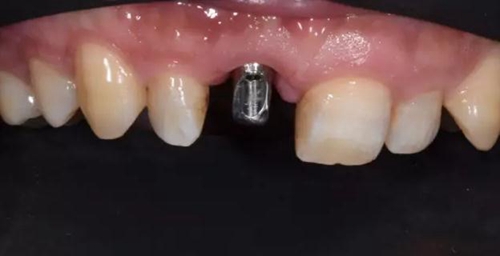

評估C先生身體狀況和口腔內(nèi)情況后。選擇了種植修復(fù)。

種植體植入后